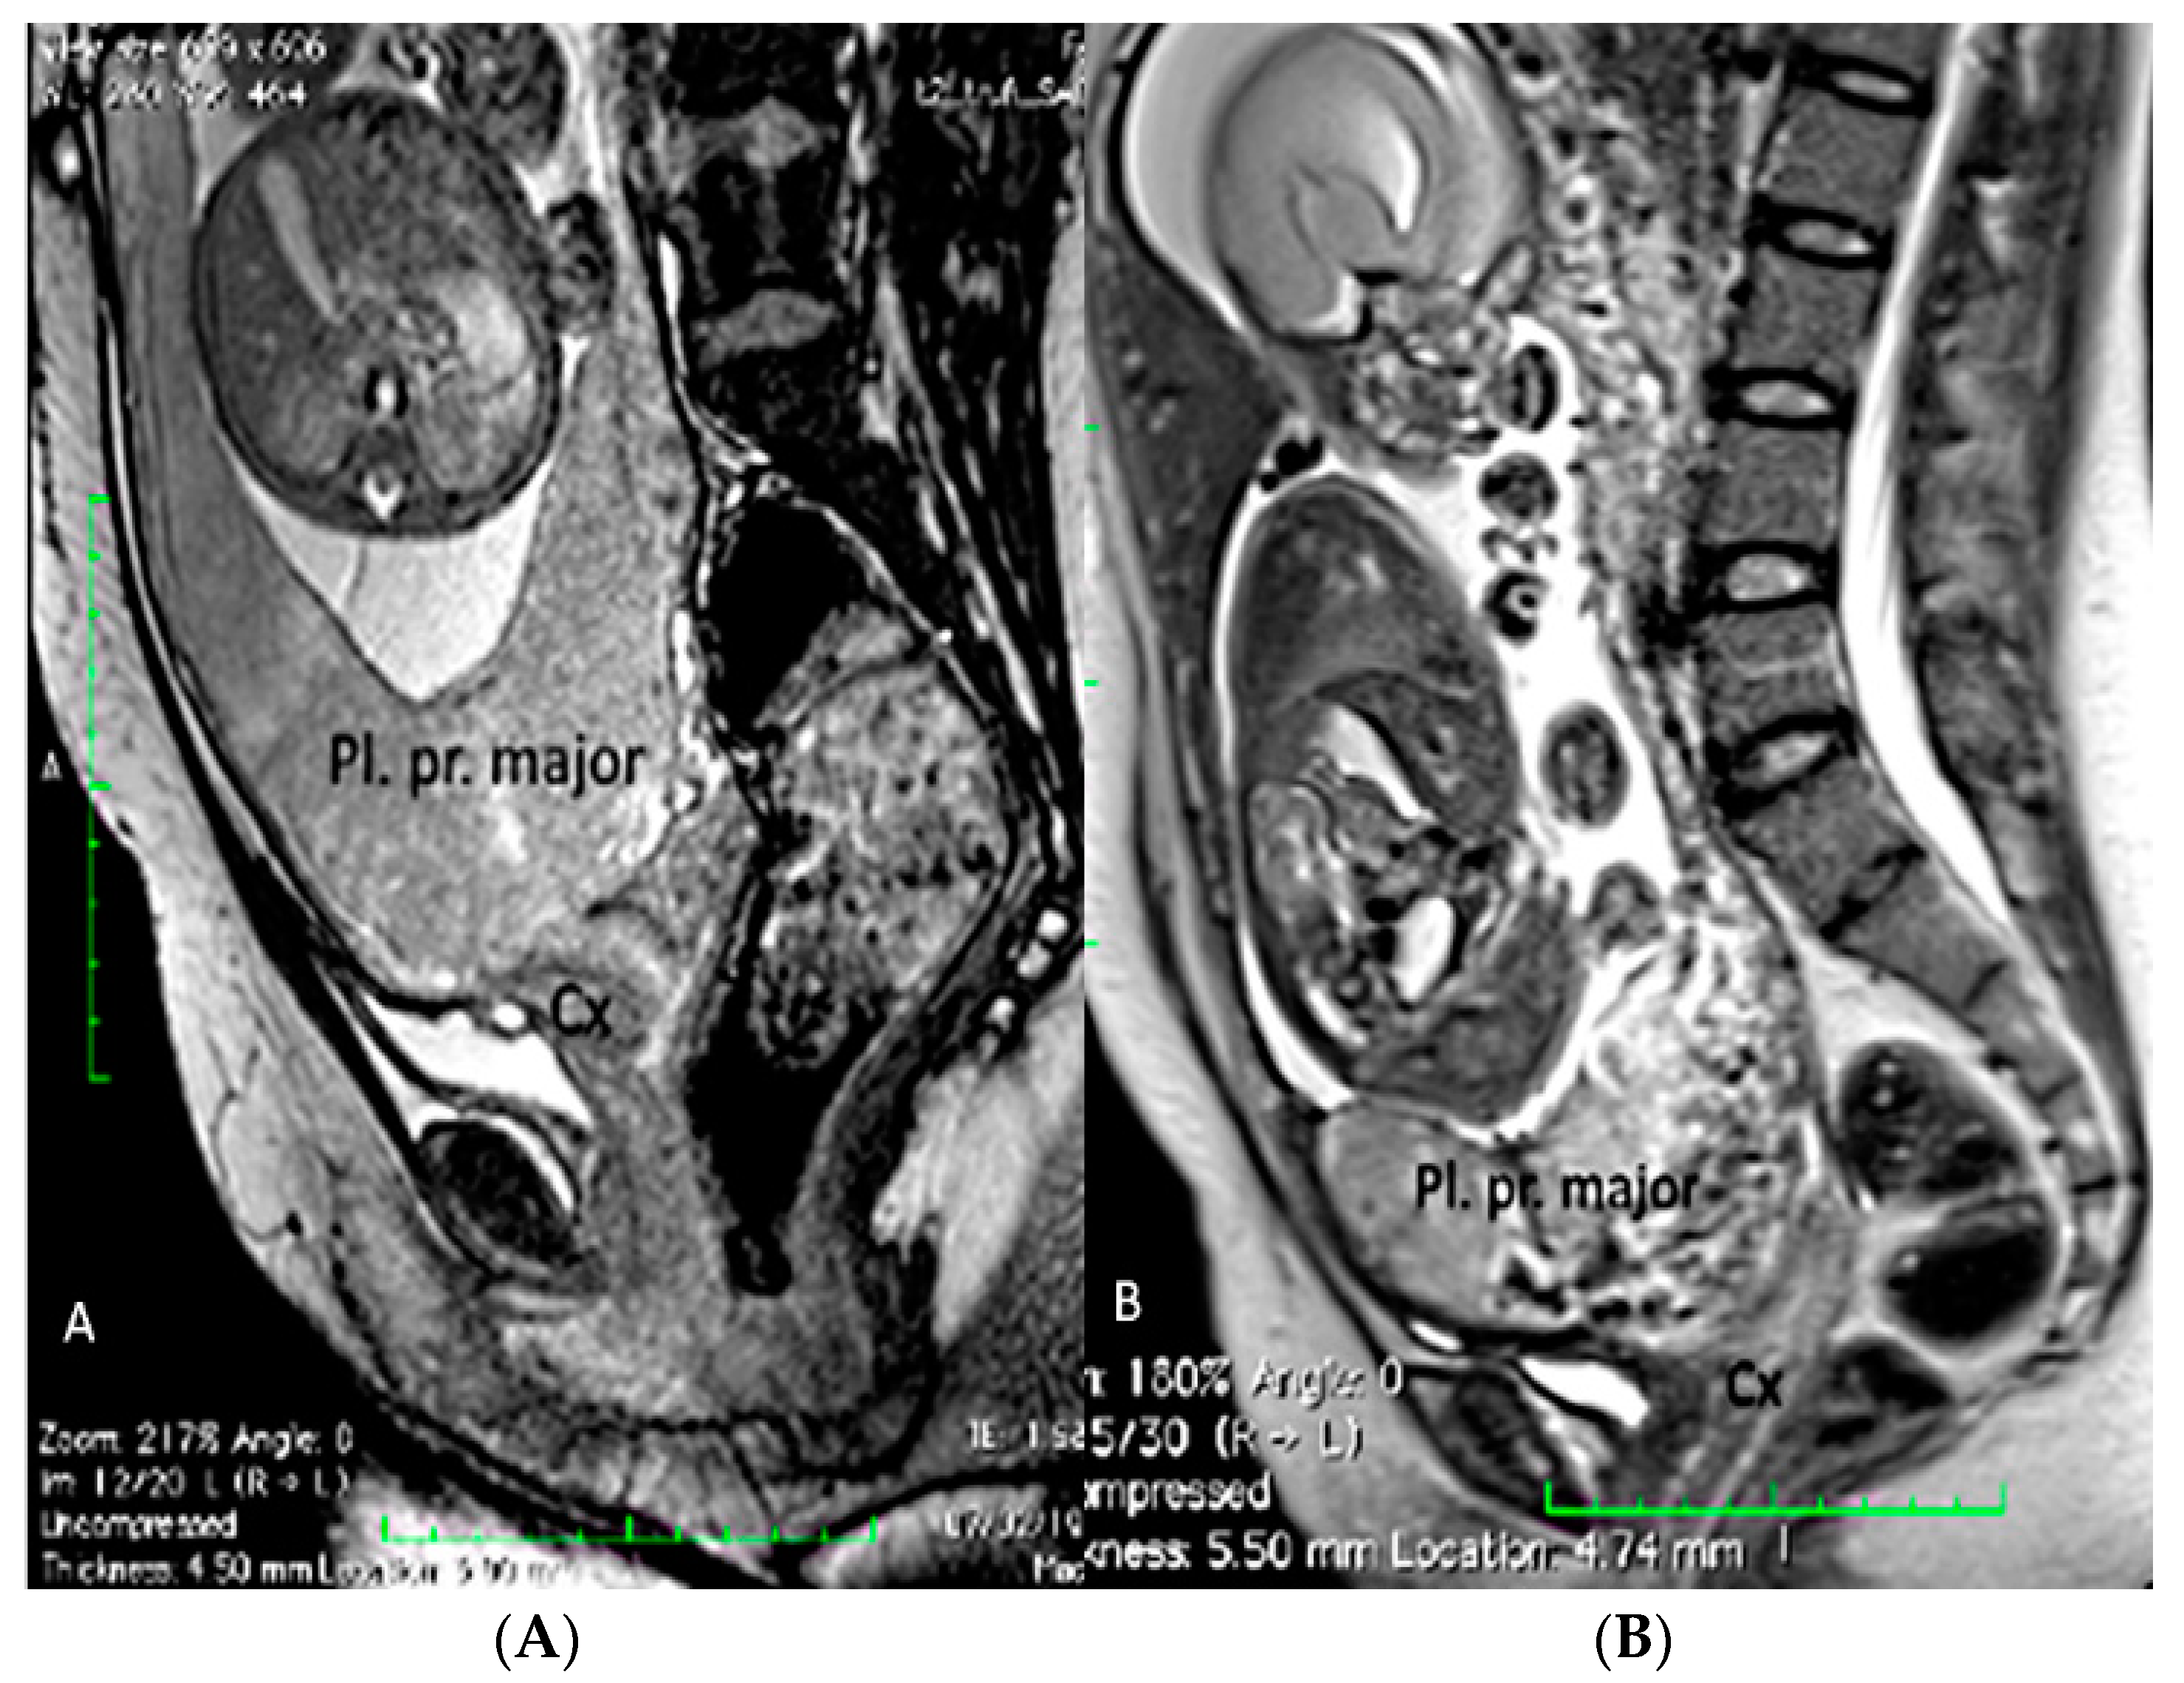

3.1.2. Placenta Praevia